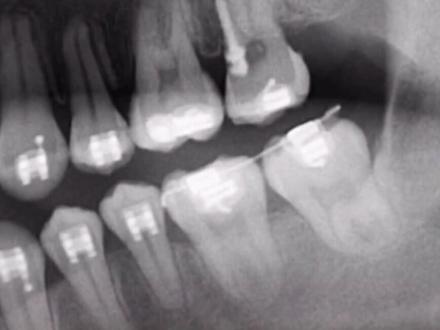

大家好,我是钢牙小董,有很多抖音的朋友问我的牙这么齐,为什么要这么挤,我是缺失六号牙之后,齐号牙被立式牙挤倒了,立式牙长出来也是倒的。之后我就无意间的刷到了这个视频, 他的下牙是跟我的牙形一样的,把七号牙跟八号牙往前移一位当做正常牙使用。 由于我长时间的缺牙导致我咬合紊乱,他要先把我的紊乱调正之后再拉七号牙跟立事牙。我这个也应该属于高龄正肌的。 我会不定期分享我牙齿遇到的问题,有志同道合的朋友可以跟我来个互关。

缺牙选正肌还是选种植?按道理来讲应该是这样种牙吧, 但是我知道有一部分的病人是说能不能不做种植呢?那正极不是有一个关闭间隙的技术吗?把风给我关上,这样不就好了吗?的确如此,这是很大部分病人的诉求,我也能理解,包括我自己也是一样。 嗯,如果我要是说这中一颗牙,实际上说心里话,哎呀,我也有点恐惧。那 如果正极声把风关上,这多好啊,这是第一个诉求。那么事实上可不可以这样呢?非常可以, 我想我的成人病人有一大部分病人都是这个原因。嗯,那以这个病人为例吧,你看他缺了四个大牙, 那么应该去种植。但是我们在想正极同时还有念形的变化。 可以这样说,如果这个病人缺牙,正极是可以把风关上的。正极的这个技术是可以实现的。但是如果这个病人面型非常好,很标准, 这么做其实容易造成面型辨别,我觉得这样并不好。但如果这个病人像我这个病例一样是嘴秃,没有下巴,面型不好, 那这个病例就可以用正极的方法把牙缝关上,从而改变他的面型。